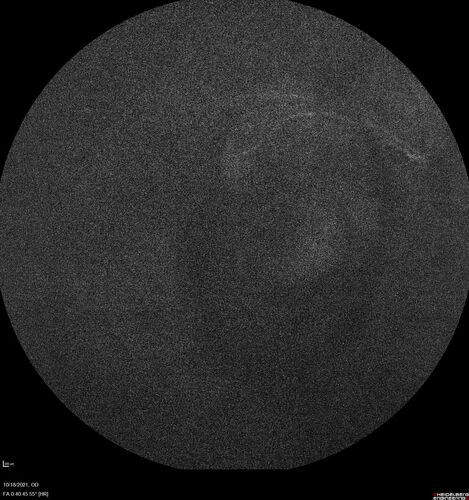

Severe Syphilitic Placoid Chorioretinitis

68 year old man 3 months ago the vision started fading in both eyes.  Just sitting here he can see some light out of his right eye. The patient denies any recent illness or travel.

VA: OD: LP, OS: 4/200

IOP: 9, 13

Anterior segment: 1+ cell/ 2+ flare OU and 2+ NS and anterior vitreous cells

Labs Reactive RPR 1:256, FTA-ABS - reactive - Patient was admitted to hospital for IV PCN and recovered vision almost completely in the left eye and some in the right eye.